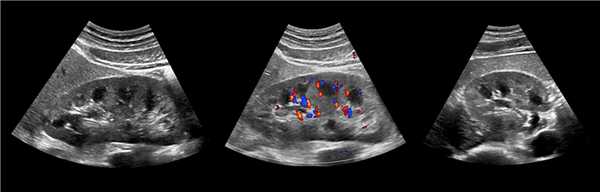

Рисунок. На УЗИ синус почки разделяет полная паренхиматозная перемычка (1, 2). В таких случаях разграничить удвоение почки от гипертрофии колонны Бертини поможет экскреторная урография. Удвоенная почка покрыта общей фиброзной капсулой. Полное удвоение предполагает наличие двух лоханок, двух мочеточников и двух сосудистых пучков. Неполноудвоенная почка (3) питается одним сосудистым пучком, мочеточник может быть удвоен вверху и впадать в мочевой пузырь одним или двумя устьями. Удвоение ЧЛК и мочеточников — фактор риска развития патологии (пиелонефрита, гидронефроза и др.).

Рисунок. На УЗИ синус почек широкий, неоднородной эхоструктуры (1, 2). На фоне гиперэхогенного жира гипоэхогенный очаг округлой формы (2), при ЦДК междолевые сосуды проходят через гипоэхогенную зону без смещения (3) — это гипоэхогенный жир. При ожирении липоматоз синуса можно ошибочно принять за атрофию паренхимы.

Мочеточник, малые и большие чашечки в норме не видно на УЗИ. Существует три типа расположения лоханок: интра-, экстраренальный и смешанный (частично внутри почки, частично вне ее). При интраренальном строение просвет лоханки в раннем возрасте до 3 мм, в 4-5 лет — до 5 мм, в пубертате и у взрослых — до 7 мм. При экстраренальном и смешанном типе строения — 6, 10 и 14 мм, соответственно. При переполненном мочевом пузыре лоханка может увеличиваться до 18 мм, но через 30 минут после мочеиспускания сокращается.

Рисунок. Независимо от наполнения мочевого пузыря на УЗИ видно лоханку смешанного (1, 2) и экстраренального (3) расположения.

Рисунок. У детей до 1 года на УЗИ синус почки определяется слабо, анэхогенные пирамиды можно ошибочно принять за расширенный ЧЛК (1). На УЗИ в воротах почки линейная гипоэхогенная структура похожа на расширенную лоханку (2); при ЦДК видно, что это сосуды (3).